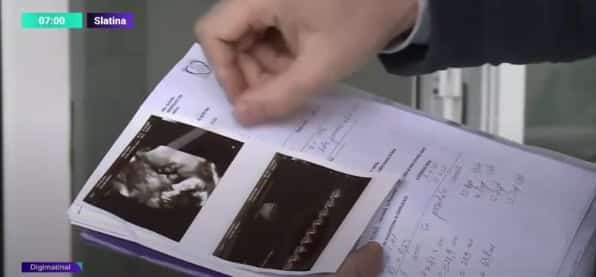

„Trebuie precizat că rangul maternităţii noastre ne permite observația pacientului timp de trei zile. Poate o să vă întrebaţi de ce pacientul nu a fost transferat imediat, dar iniţial pacientul a avut o situaţie favorabilă care nu a necesitat transferul.

Ulterior sunt consemnate toate demersurile noastre de transfer şi a fost trecut în foaia de observaţie şi nu pot să vă spun de ce nu s-a realizat acest lucru”, a declarat Radu Ene, director medical la Spitalul Slatina.

Tatăl fetiței decedate a depus plângere la Colegiul medicilor, la Parchetul de pe lângă Tribunalul Olt și la Poliție, iar oamenii legii au început deja o anchetă.

Conducerea spitalului județean Slatina a declanșat propria anchetă în acest caz.